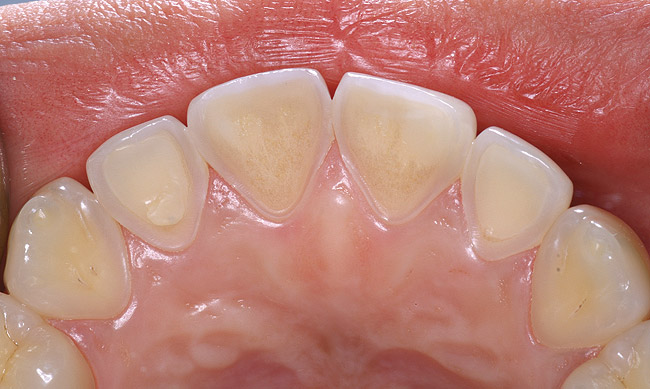

If a patient has risk factors that can contribute to dental erosion, an examination will reveal clinical signs and symptoms of dental erosion. It is unlikely that dental erosion will be seen without other contributing factors. Tooth wear and abrasion typically occur in combination with dental erosion. In the clinical evaluation of tooth surfaces for the diagnosis of erosion, what is typically seen are smooth, shiny surfaces of the teeth where the usual anatomic form of the tooth should be. In patients ingesting very acidic diets, the facial surfaces of anterior teeth are very smooth, and if the beverages being ingested have high sugar content, these teeth may have caries at their facial gingival margins (Figure 1). The occlusal surfaces of posterior teeth in the more advanced stages of erosion due to regurgitation may have extensive exposed dentinal areas with loss of anatomic form (Figure 2). In some cases, the chemical erosion combined with toothbrush–toothpaste abrasion can remove all the enamel, leaving only the dentin exposed (Figure 3). These teeth may exhibit sensitivity. Posterior teeth with restorations may demonstrate fillings that are higher than the surrounding occlusal surfaces of the enamel. Anterior teeth may demonstrate more incisal translucency due to tooth loss at the incisal edge. In patients with the eating disorder bulimia nervosa, who vomit, the hydrochloric acid causes extensive damage to the lingual surfaces of the anterior teeth, where the enamel is lost, leaving exposed dentin (Figure 4).

Figure 4  A patient with history of bulimia has dental erosion on the lingual surfaces of her maxillary incisors.

Figure 4